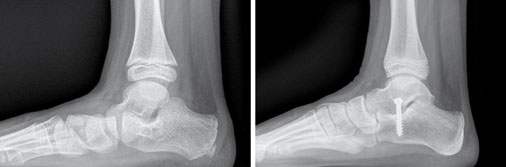

Bei fehlendem Behandlungserfolg und fortschreitender Schmerzsymptomatik kann ab dem 10. Lebensjahr eine „kleine“ operative Therapie in Betracht gezogen werden. Eine gängige Methode ist die subtalare Arthrorise, bei der durch eine Schraube eine Blockade der Bewegung im unteren Sprunggelenk erzielt wird. Dies führt zu einer dauerhaften Korrektur der Fehlstellung.

Röntgenbild eines Knick-Senk-Fußes vor und am Ende der Behandlung (Arthrorise)